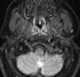

Enlarged adenoids

Adenoid hypertrophy (enlarged adenoids) is the unusual growth (hypertrophy) of the adenoid (pharyngeal tonsil) first described in 1868 by the Danish physician Wilhelm Meyer (1824–1895) in Copenhagen. He described a long term adenoid hypertrophy that will cause an obstruction of the nasal airways. [Source: Wikipedia ]